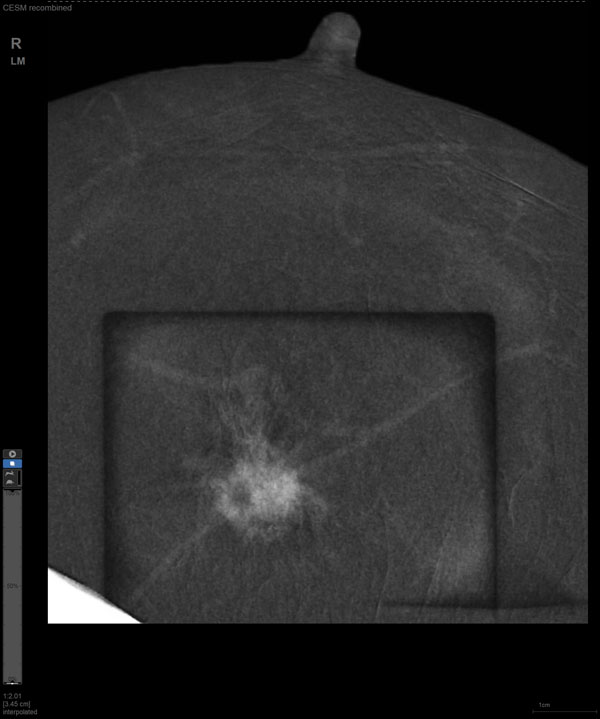

某患者增强磁共振成像MRI显示肿瘤周边有活性,中心区域有组织坏死。为得到准确的病理结果,穿刺靶区需避开肿物坏死区域。在与患者主管医生充分讨论后,放射科医生为患者行CEM引导下穿刺活检术。术中,CEM检查肿物同样显示为环形强化,巧妙避开坏死区域后,穿刺靶区选择了肿物增强早期明显强化区域,术程顺利,仅用时15分钟。术后该患者病理结果为浸润性导管癌Ⅱ级。

CEM作为近年来新兴的乳腺成像方法,是在传统乳腺X线摄影的基础上,通过静脉注射碘对比剂,用高低两种能量的X线摄影通过计算机进行能量减影处理,得到的减影像能突出显示病灶强化特征的一项新技术。其优势在于,既能显示乳腺病变的形态学特征,又能反映病变新生血管的血供情况,被越来越多地应用于临床。